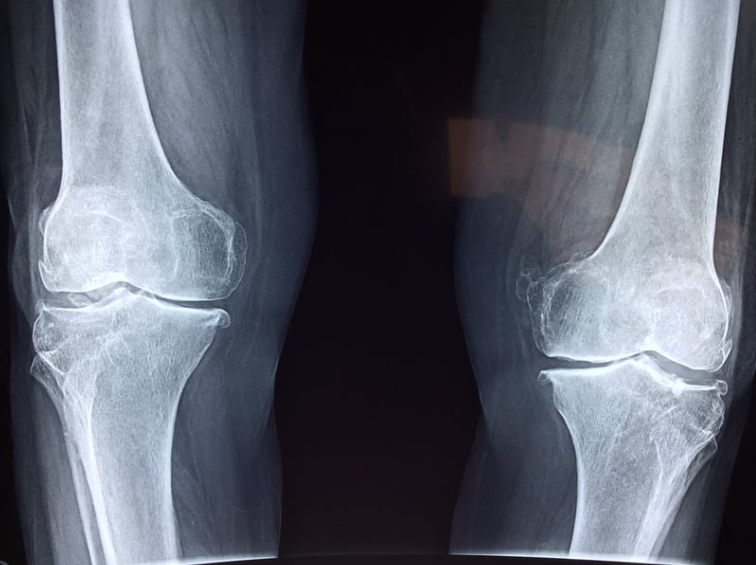

Хронический артрит крупных суставов – коленных, тазобедренных, плечевых – занимает особое место среди заболеваний опорно-двигательного аппарата. Эта патология формируется под влиянием трех ключевых факторов: механического (хронические перегрузки и травмы), воспалительного (аутоиммунные процессы) и дегенеративного (возрастные изменения метаболизма хрящевой ткани). Особая опасность хронического артрита заключается в его прогрессирующем характере. При отсутствии своевременного комплексного лечения в суставе происходят необратимые изменения: Клинически это проявляется упорным болевым синдромом, особенно при стартовых движениях, ночными болями на поздних стадиях, прогрессирующим ограничением функции сустава и развитием анкилозов в 15-20% случаев. Согласно данным многоцентровых исследований, у 60% пациентов с нелеченым хроническим артритом в течение 5-7 лет развивается деформирующий остеоартроз III-IV стадии, требующий эндопротезирования. При этом у 40% больных уже на ранних стадиях отмечает

Хронический артрит крупных суставов – коленных, тазобедренных, плечевых – занимает особое место среди заболеваний опорно-двигательного аппарата. Эта патология формируется под влиянием трех ключевых факторов: механического (хронические перегрузки и травмы), воспалительного (аутоиммунные процессы) и дегенеративного (возрастные изменения метаболизма хрящевой ткани).

Особая опасность хронического артрита заключается в его прогрессирующем характере. При отсутствии своевременного комплексного лечения в суставе происходят необратимые изменения:

• Деструкция хряща с обнажением субхондральной кости

• Формирование остеофитов

• Фиброз синовиальной оболочки

• Атрофия периартикулярных мышц

Клинически это проявляется упорным болевым синдромом, особенно при стартовых движениях, ночными болями на поздних стадиях, прогрессирующим ограничением функции сустава и развитием анкилозов в 15-20% случаев.

Согласно данным многоцентровых исследований, у 60% пациентов с нелеченым хроническим артритом в течение 5-7 лет развивается деформирующий остеоартроз III-IV стадии, требующий эндопротезирования. При этом у 40% больных уже на ранних стадиях отмечается значительное снижение качества жизни и трудоспособности.